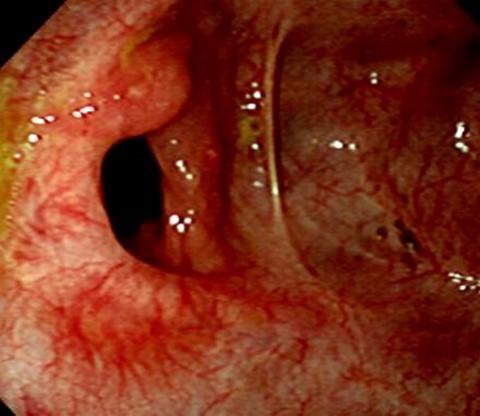

장결핵은 복통, 설사, 체중 감소를 보이는 환자를 대상으로 대장 내시경검사, 조직검사, 대장 및 소장 X-선 촬영 등을 통해 진단을 내립니다.